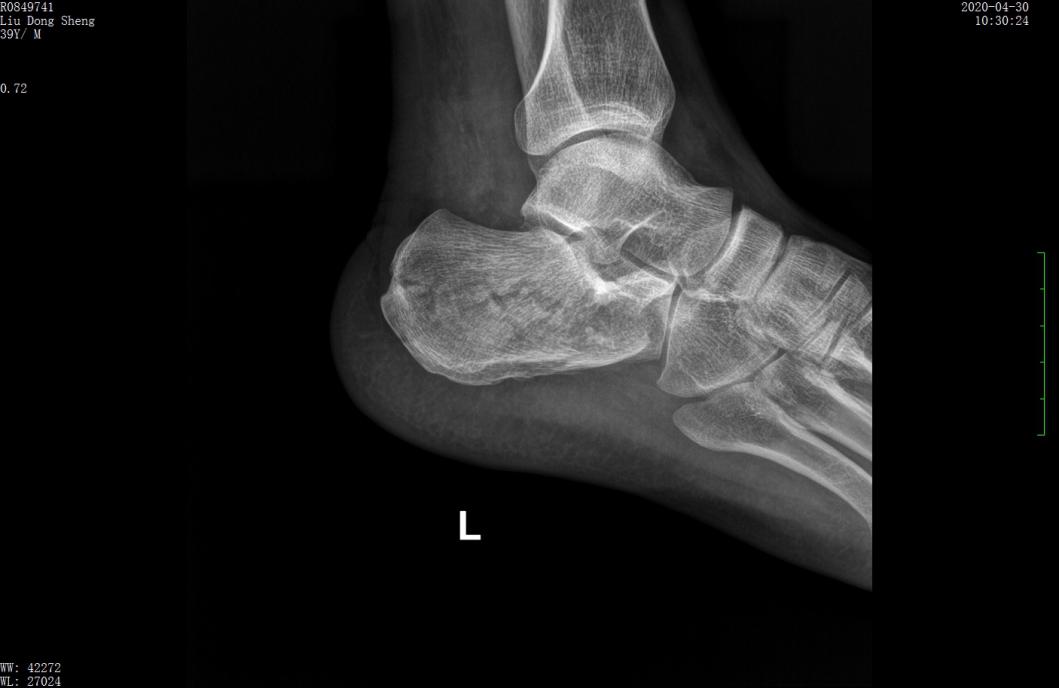

案例1影像

术前CT示跟骨严重粉碎骨折,移位明显